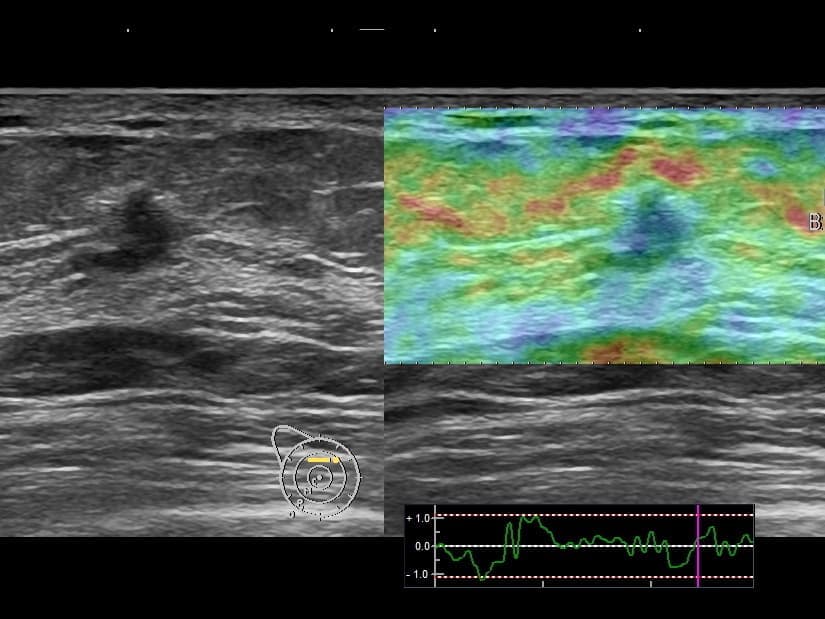

- 乳腺超音波検査:腫瘤の硬さをみるエラストグラフィーの機能もあります。若い女性の乳癌の発見にはマンモグラフィーよりも超音波検査が有用な場合もあります。